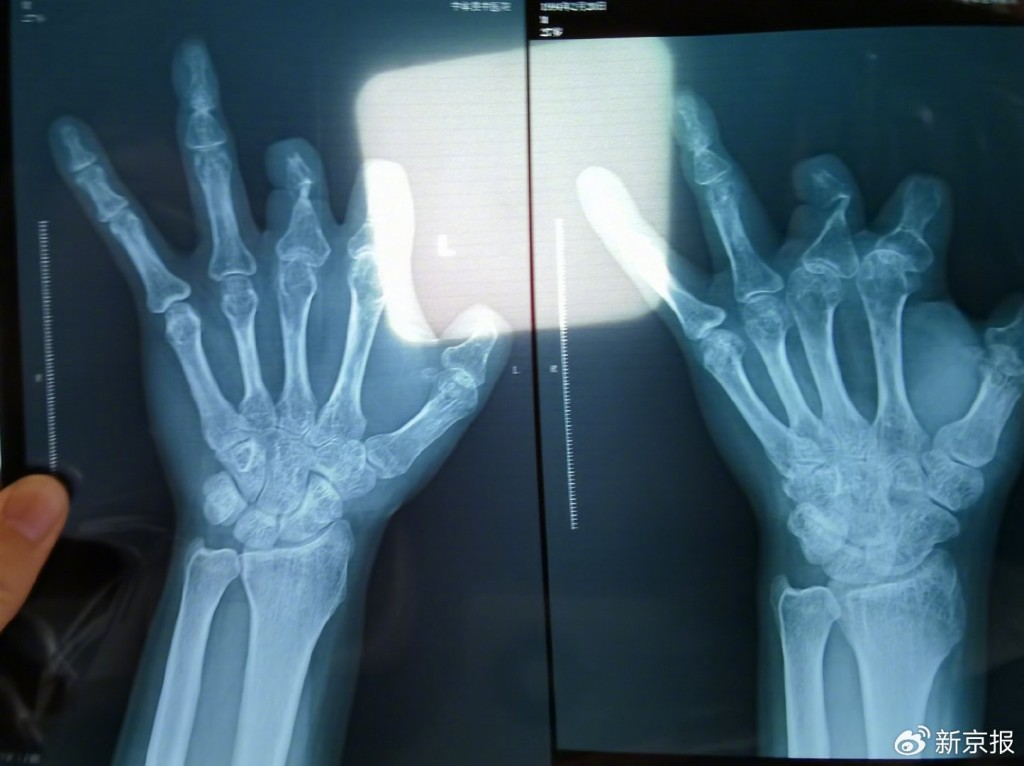

王海森發現體內並無植入血管吻合裝置。新京報

其中一名受害人是木工王海森,他2018年工傷斷了左手拇指,被王福建遊說購入兩個微血管吻合裝置。但術後3年,王海森拍了X光片,發現體內並無上述裝置,懷疑受騙,於是報警,揭發案件。